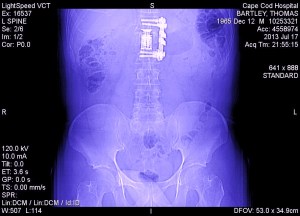

four years ago this month I fell (pretty seriously) but- I bounced.

time at this point stretched itself outup- into minute by minute segments and continued for a few months like this- there was no ‘bounce’ apparent at this point. It’s probably more like you have to crawl out of whatever crater you made on impact and you are just trying to get back to the surface-I started to keep a journal when I got out of the hospital- many many days it just says what time I got up and maybe how I felt (in like 2 or 3 words) but eventually I had entries about dressing myself and then an entry about how I would eventually stop making entries- and not to worry because I was getting better.